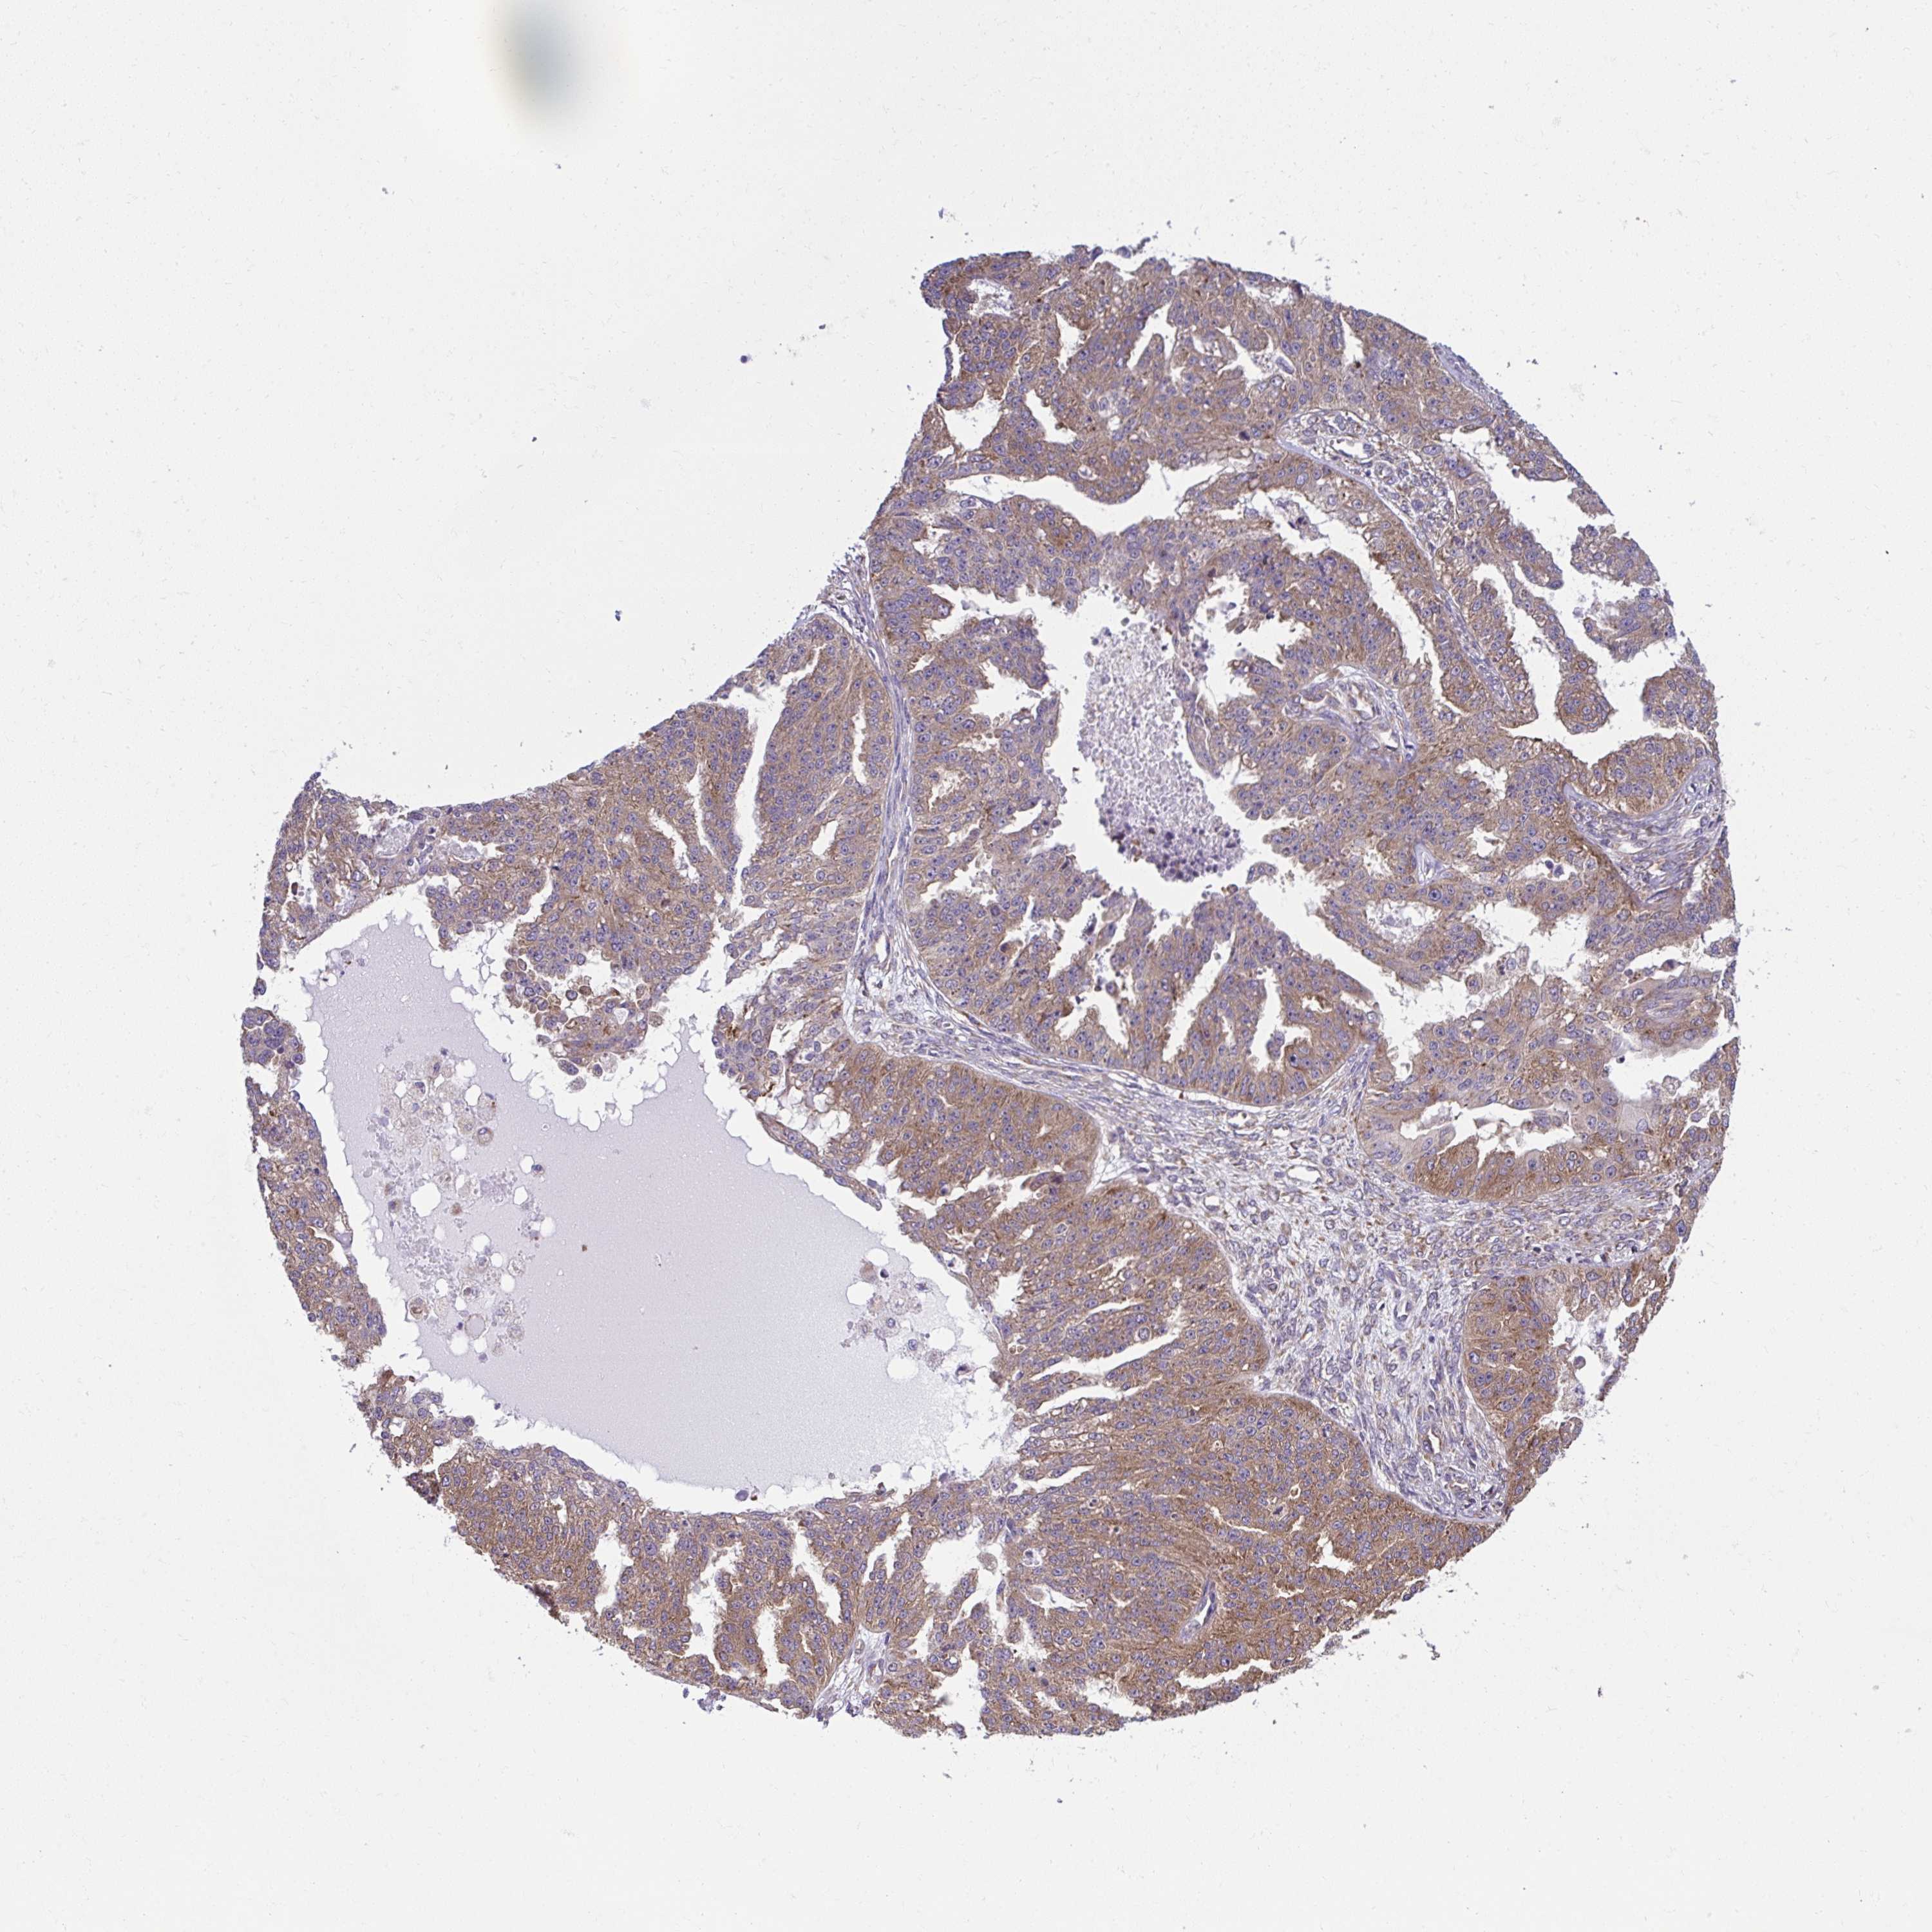

OVARIAN CANCER - Protein expressioni

A mouse-over function shows sample information and annotation data. Click on an image to view it in a full screen mode. Samples can be filtered based on level of antibody staining by selecting one or several of the following categories: high, medium, low and not detected. The assay and annotation is described here.

Note that samples used for immunohistochemistry by the Human Protein Atlas do not correspond to samples in the TCGA dataset.

Antibody stainingi

Antibody staining in the annotated cell types in the current human tissue is reported as not detected, low, medium, or high, based on conventional immunohistochemistry profiling in selected tissues. This score is based on the combination of the staining intensity and fraction of stained cells.

Each image is clickable and will lead to virtual microscopy that enables deeper exploration of all samples and also displays staining intensity scores, fraction scores and subcellular localization as well as patient and tissue information for each sample.

Antibody HPA056586

Cystadenocarcinoma, serous, NOS

Carcinoma, endometroid

Cystadenocarcinoma, mucinous, NOS

Carcinoma, NOS